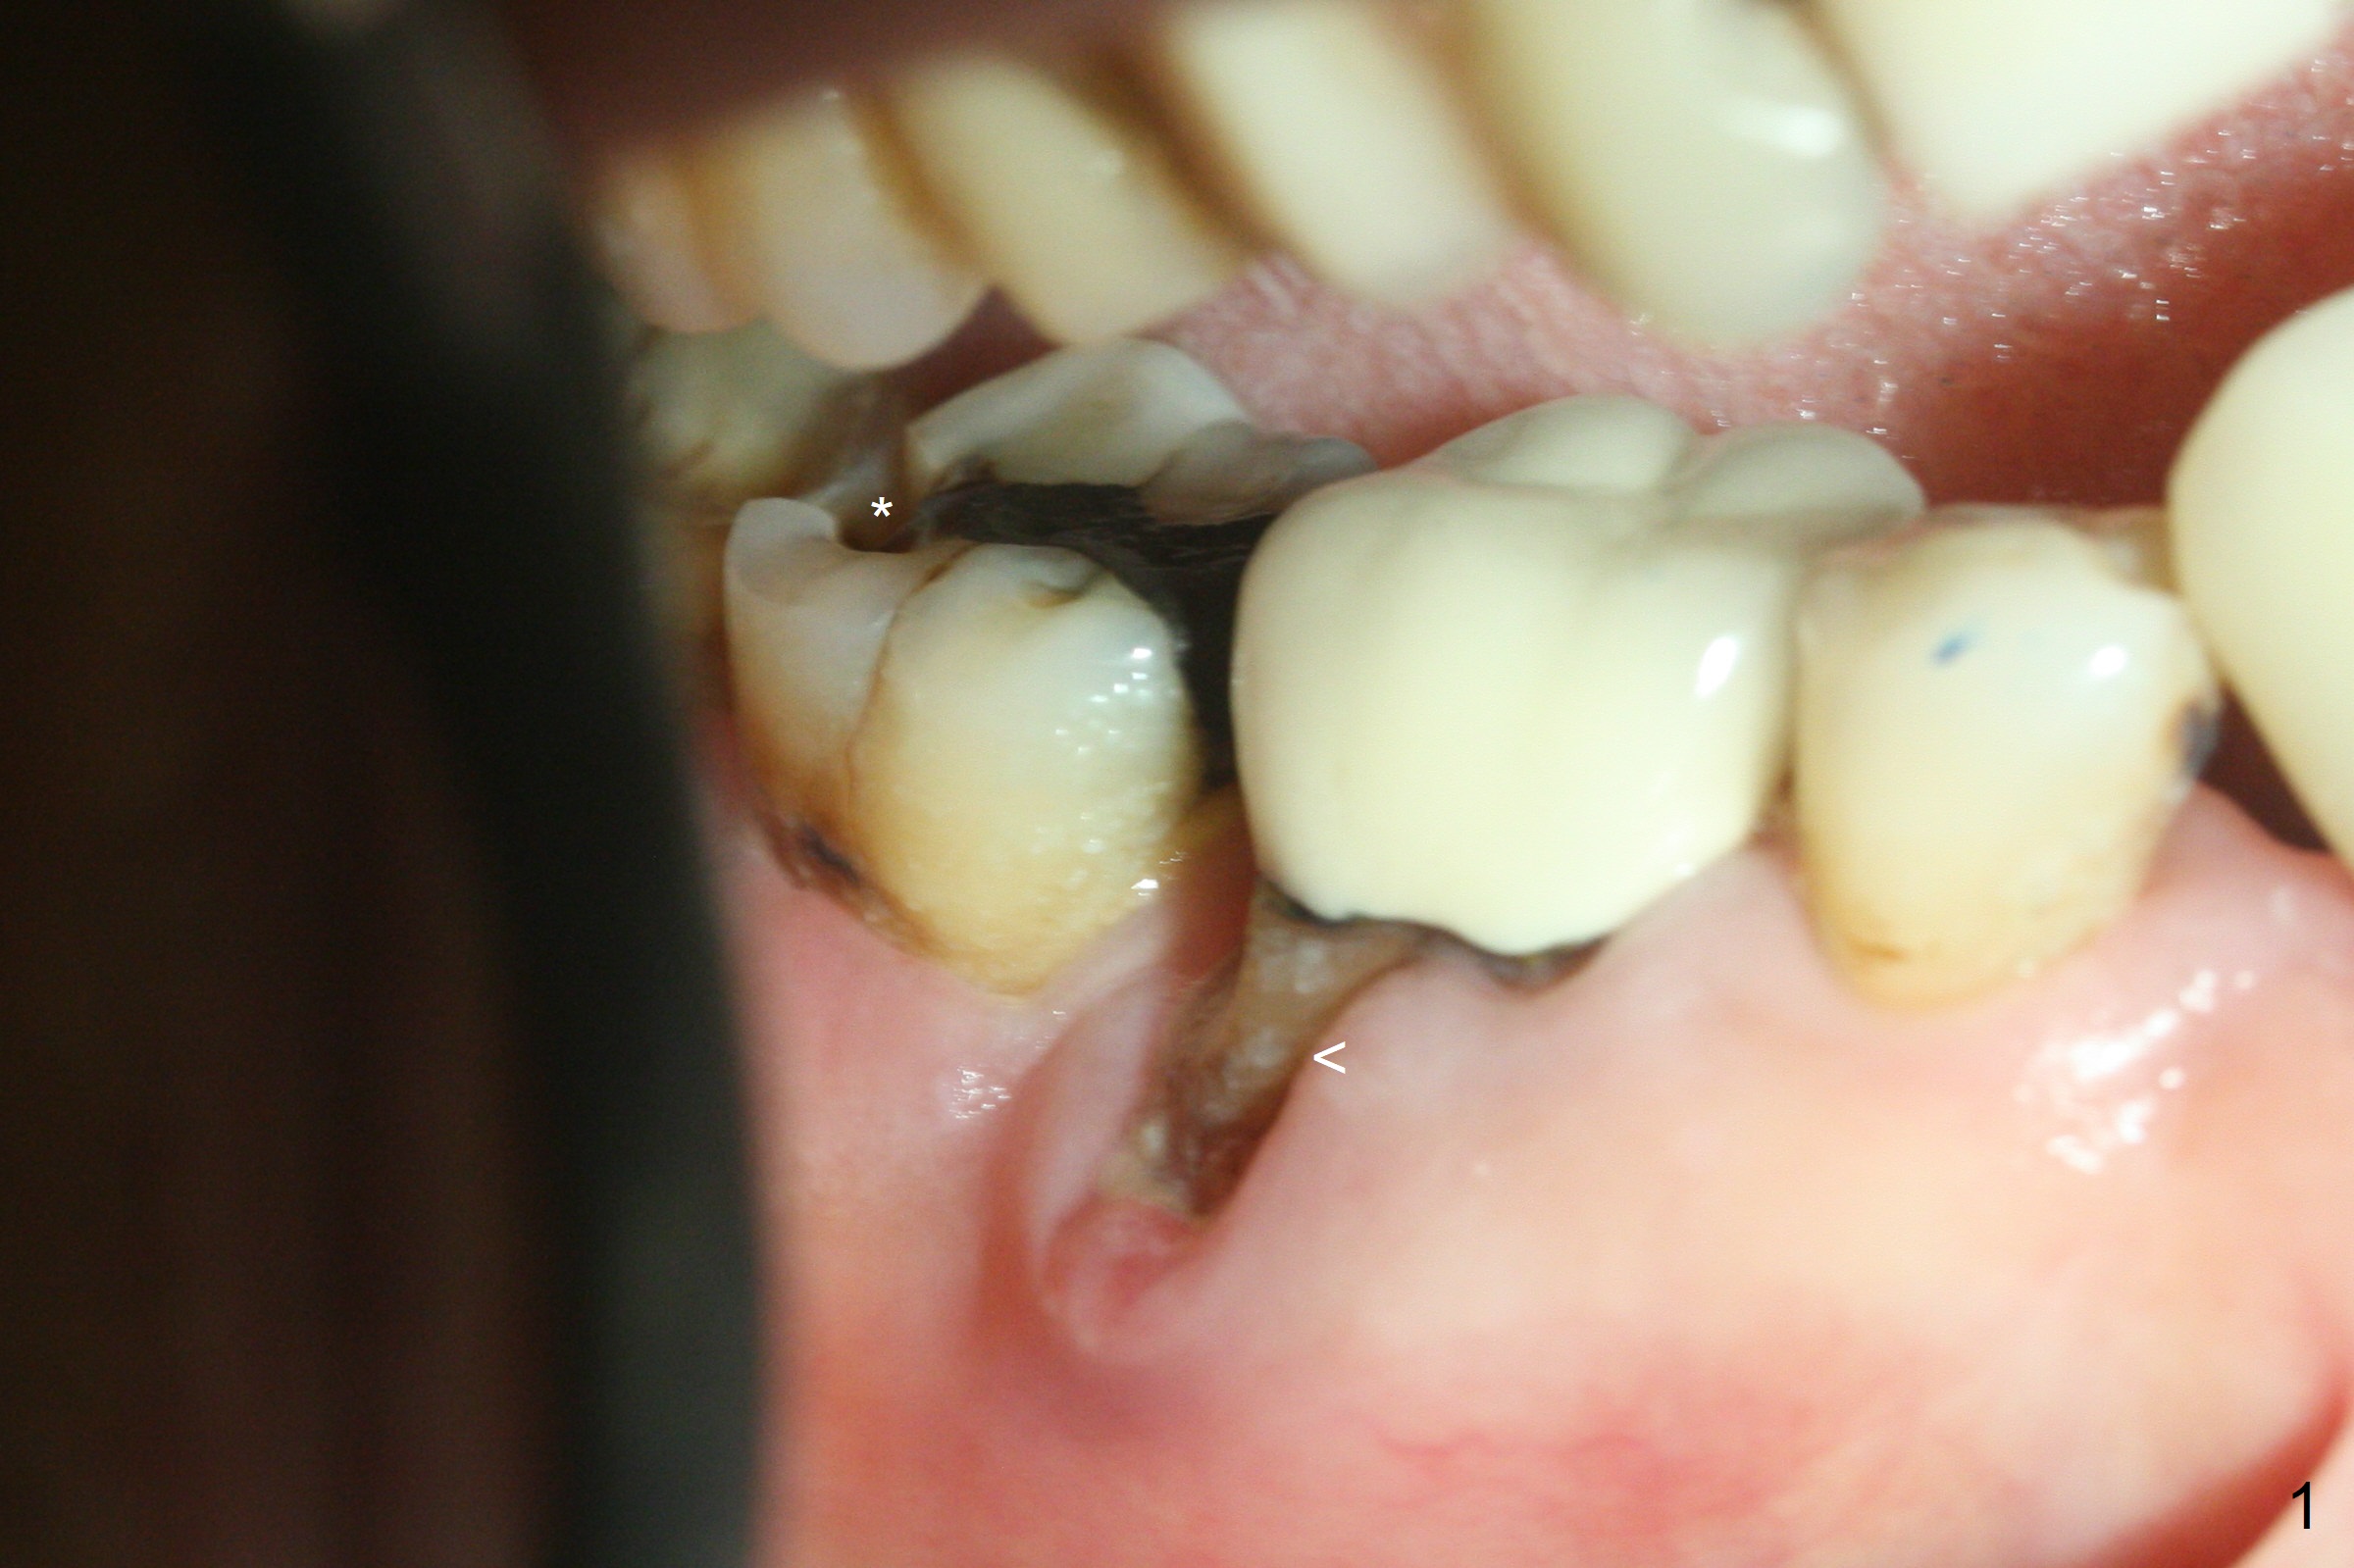

Although the tooth #30 has distobuccal root exposure (Fig.1 <), it is asymptomatic.  In contrast the tooth #31 with the distoocclusal caries (*) is symptomatic.  After use of 2 mm drill for 18 mm (lingual gingival margin), a calculated parallel pin is inserted (Fig.2 (D: 2 distal roots of the tooth #30)).  It appears that a 11.5 mm long implant is appropriate for the site; a 5 mm cuff is expected.  Following 4.8 mm drill, a 5.5x11.5 mm implant is placed initially (Fig.3) with an apical space (*) and clearance from the Inferior Alveolar Canal (red dashed line).  The implant is placed deeper with placement of a 6.5x4(5) mm abutment and bone graft (*, Fig.4,5).  After placement of collagen membrane over the graft, an immediate provisional is fabricated (Fig.6 P) with clearance from the opposing tooth (Fig.7 *).  There is no bone loss 3.5 months postop (Fig.8).  In fact the abutment has not been seated completely since its placement (Fig.4,5,8).  The crown/abutment dislodges 3 years 3 months post cementation (Fig.9).  The latter occurs for long incubation time because of opposing partial denture (Fig.10).  After trimming proximal surfaces (Fig.11: arrowheads), the abutment remains incompletely seated (Fig.11) due to possible crestal bone interference (Fig.11 *).  The smaller abutment by itself remains unseated (Fgi.12).  One size small one is completely seated (Fig.13).  Impression is taken.  Two weeks later the abutment margin is supragingival.  After screw torque at 20 Ncm, the crown is cemented with access hole.  Excess cement is removed.